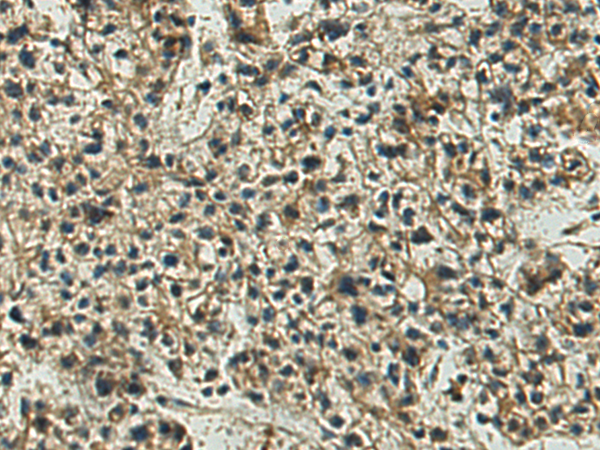

分类: 科研抗体货号: P07217别名: EB1; SCAF1; SCAFI; SIG81; COX7AR; COX7RP应用: WB,IHC反应种属: Human, Mouse

分类: 科研抗体货号: P07218别名: COX11P应用: WB,IHC反应种属: Human, Mouse

分类: 科研抗体货号: P07216别名: NOC4, COX4NB, C16orf2, C16orf4, FAM158B应用: WB,IHC反应种属: Human, Mouse, Rat

分类: 科研抗体货号: P07243别名: DCIR; LLIR; CD367; DDB27; CLECSF6; HDCGC13P应用: WB,IHC反应种属: Human

分类: 科研抗体货号: P07239别名: HLP; CP33; CP34; CYP3A; NF-25; CYP3A3; P450C3; CYPIIIA3; CYPIIIA4; P450PCN1应用: WB,IHC反应种属: Human

分类: 科研抗体货号: P07212别名: AOM; ANFH; SEDC; STL1; COL11A3应用: WB,IHC反应种属: Human, Mouse, Rat

分类: 科研抗体货号: P07237别名: AHH, AHRR, CP11, CYP1, P1-450, P450-C, P450DX应用: WB,IHC反应种属: Human, Mouse, Rat